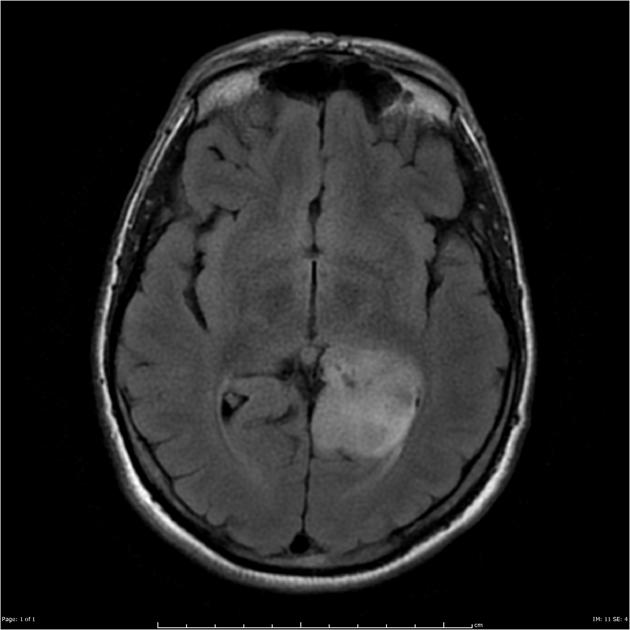

After a careful H&P with attention to neurologic symptoms, time of onset and rate of increase, imaging is critical to localization and diagnosis. Surgery, including a complete debulking if possible is the first line treatment, and sets the stage for the next step. Imaging is predominantly MRI based, with T1 ±gad, T2, FLAIR, diffusion weighted, and gradient echo sequences to identify and localize the extent of disease. Surgery is used to debulk the tumor completely if possible, and if not to obtain tissue for diagnosis.

Imaging

GBM FLAIR

Radiotherapy General Fields

The treatment fields for HGG in pediatrics, similar to adults is the imaging enhanced region plus a margin. The initial GTV is the MRI T2 abnormality (edema). The initial CTV = GTV + 1.5 cm, corrected for anatomical barriers. The usual dose to this volume is 50.4 - 54 Gy at 1.8 Gy/fraction. The second GTV (boost GTV) is the T1+gadolinium enhancement. The second CTV=GTV+1 cm. This is then carried to 59.4 Gy.

• initial GTV = T2 or FLAIR mri image

• The CTV is the T2 GTV+1.5 cm margin, with corrections for anatomical barriers (⇒ 50-54 Gy)